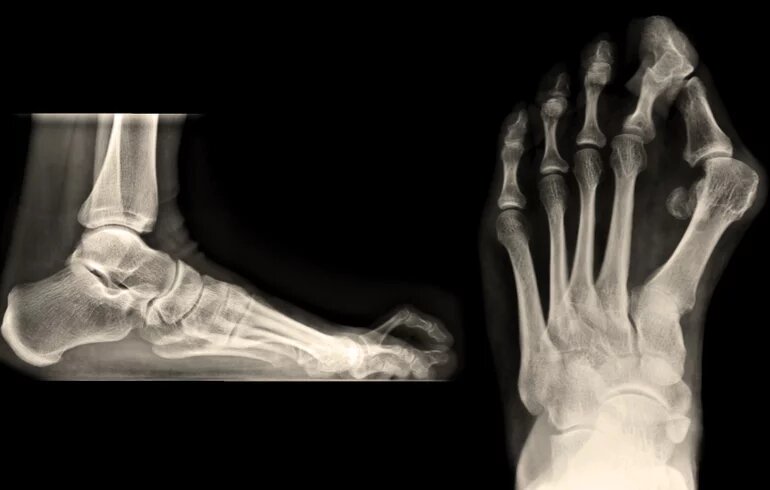

• Röntgenvizsgálat: segítségével képet kaphatunk csontokról, ízületekről és a gerincről, és segíthet az esetleges törések, elmozdulások, ciszták vagy más eltérések felismerésében.